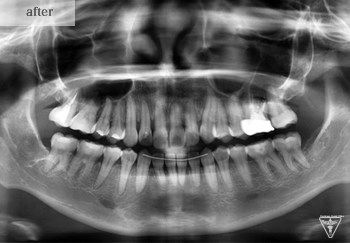

治療後

治療後

治療後